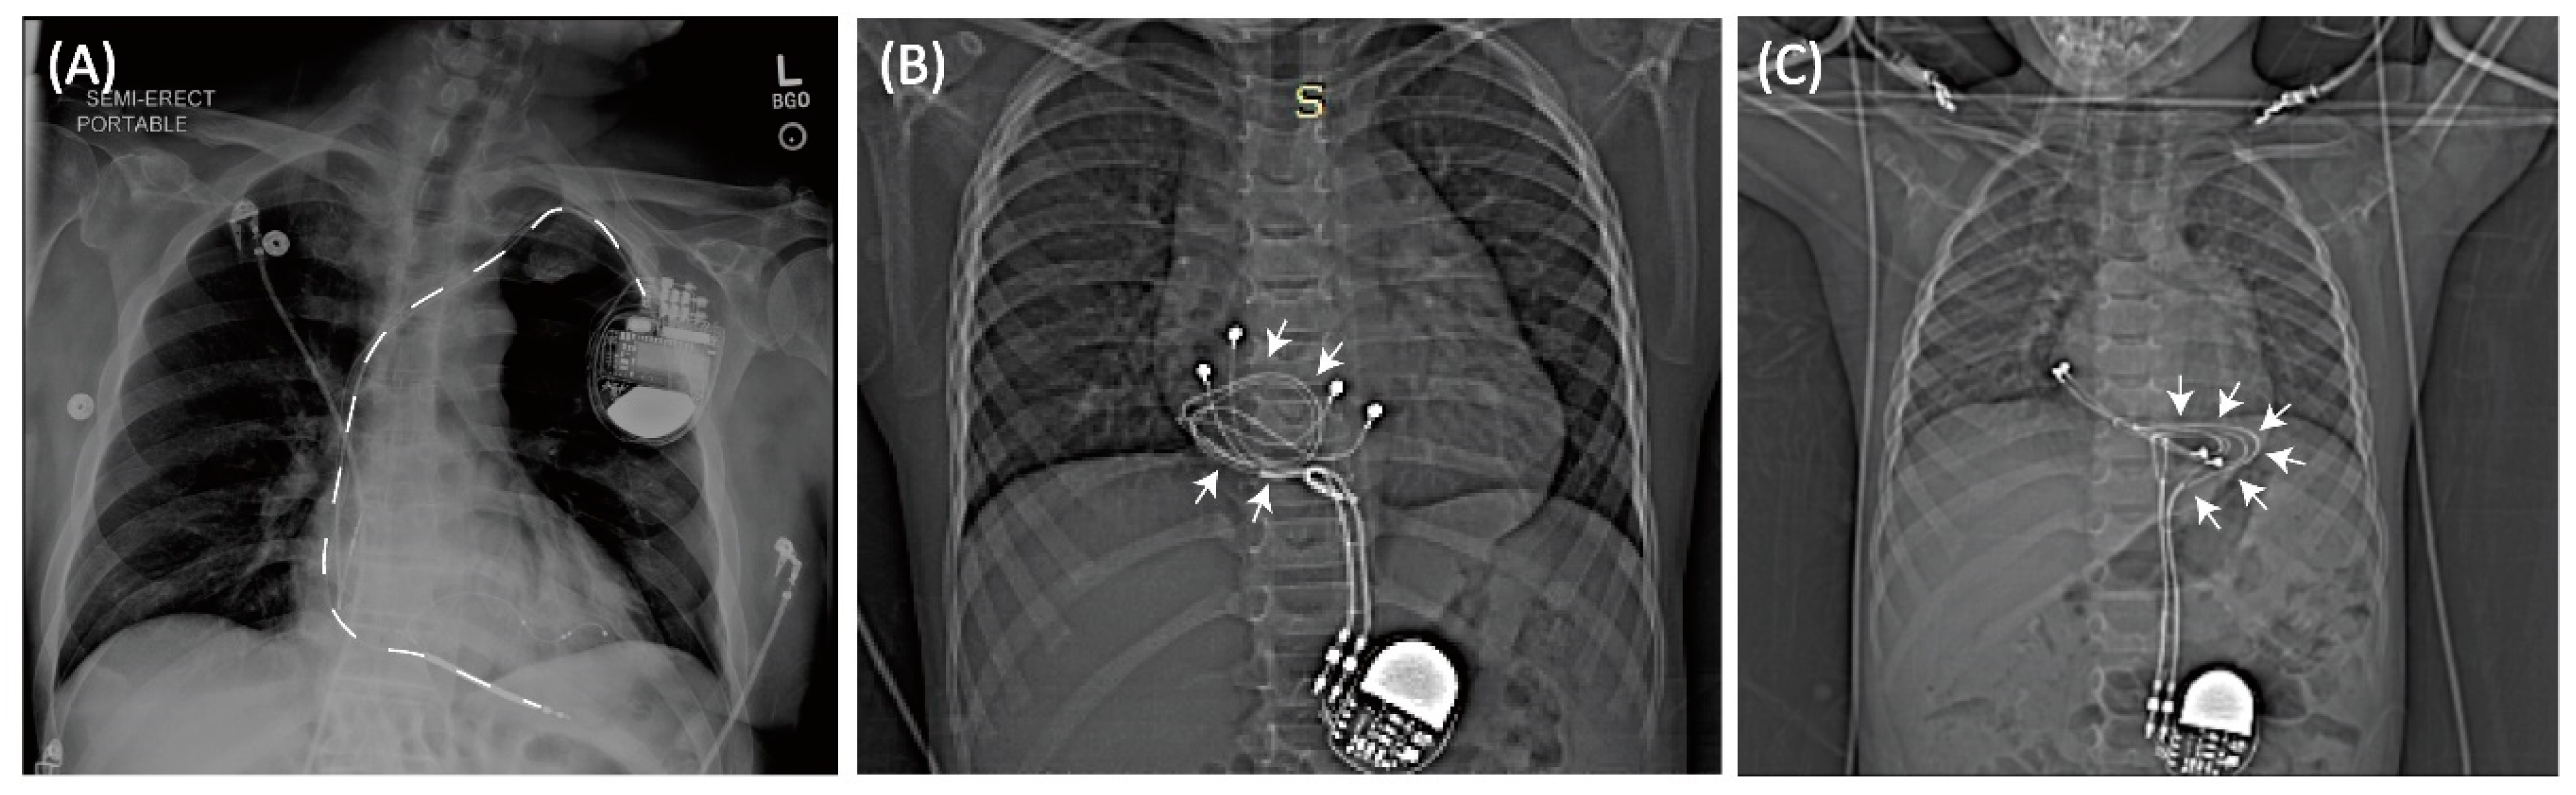

Figure 1.

(A) Typical trajectory of an endocardial lead. Leads pass through the subclavian vein creating a stereotypical pathway in nearly all patients. In contrast, epicardial devices can have highly varied lead trajectories (B,C).